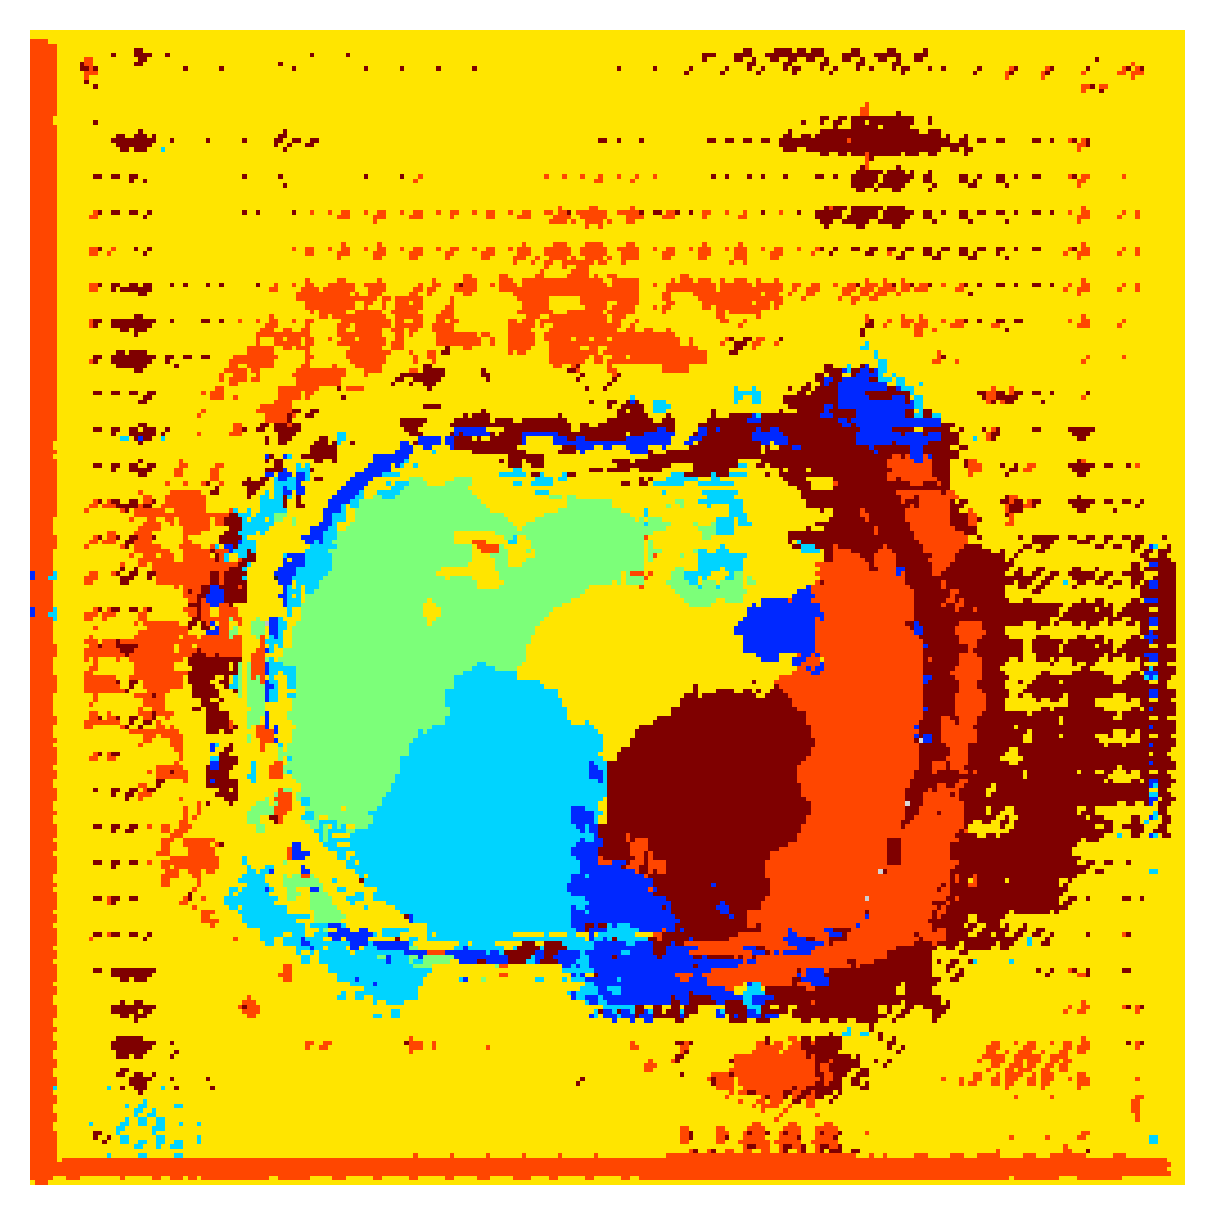

Qualitative comparison

|

|

|||

|

|

|

|

|

|

|

|

|

|

|

|

| (a) Ground truth | (b) , full | (c) , weak | (d) |

| (full) | supervision | supervision | |

|

|

|

|

|

|

|

|

|

|

|

|

| (e) | (f) | (g) | (h) CRF-loss |

In Figure 6 we provide qualitative results on a number of randomly chosen test set slices. Upon visual inspection, we can observe that training with the intensity-aware distances (particularly with and ) follows the image gradients better and is better at recovering the underlying shape than the Euclidean version. The CRF-loss seems to recover the shape of the myocardium and left ventricle to some extent, but fails entirely on the right ventricle.